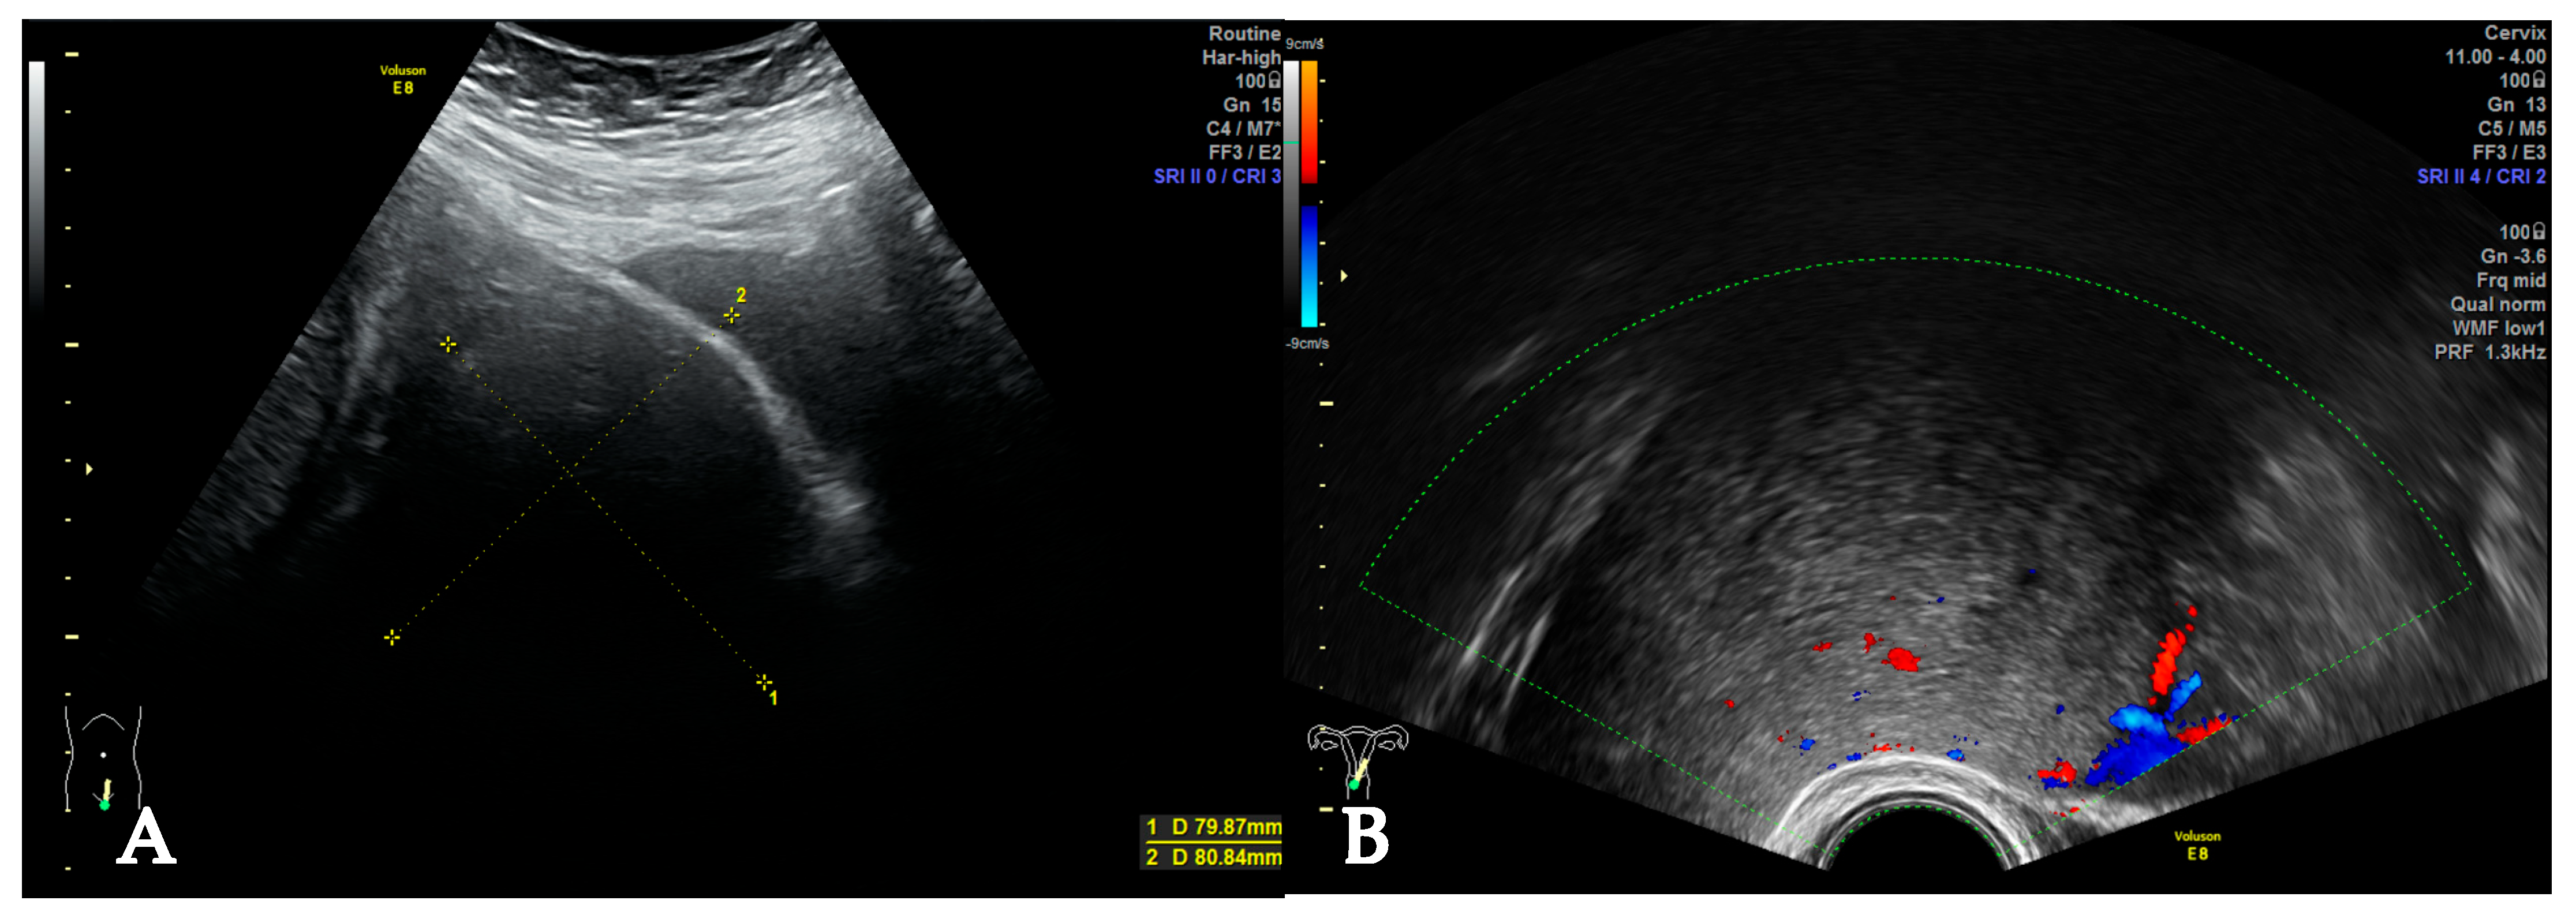

2. Case